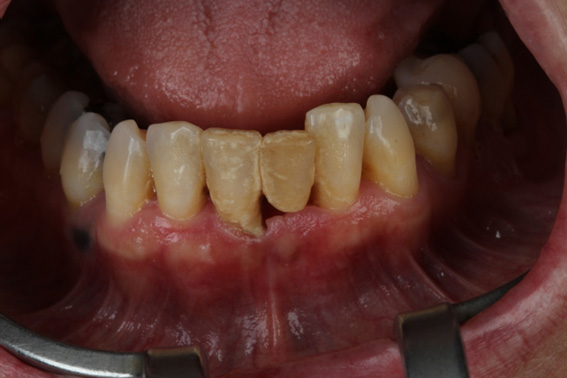

1 | Initial aspect, teeth in occlusion

2 | Initial aspect, lower elements